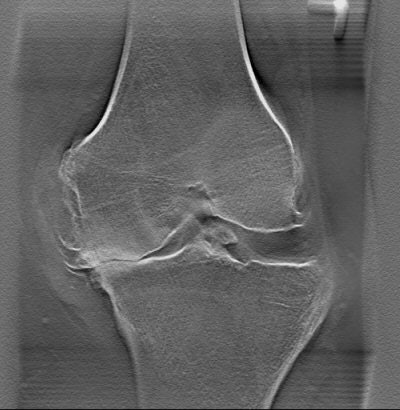

![]() |

| Single-slice view from a multiple-slice tomosynthesis knee exam. Image courtesy of Shimadzu Medical Systems North America. |